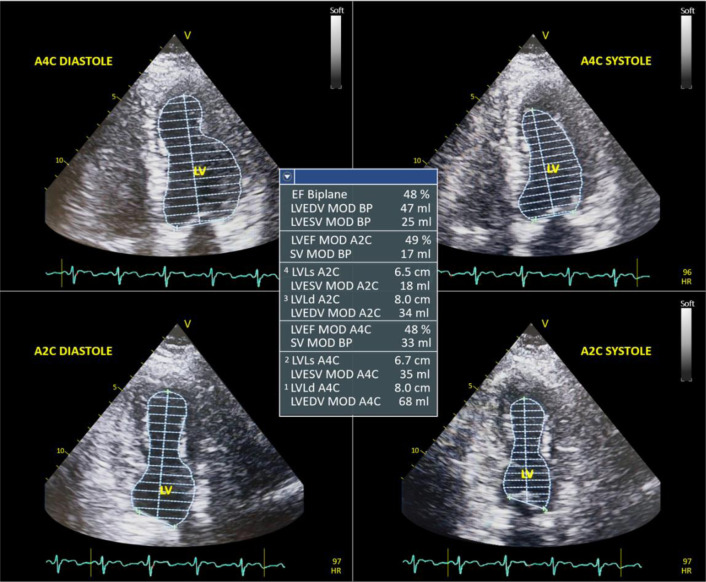

虽然钩端螺旋体病是一种公认的人畜共患疾病,但st段抬高型心肌梗死(STEMI)-模拟钩端螺旋体心肌炎的发生,伴随随后的出血和血小板减少是一种非常罕见的发现。出血和血栓形成的双重风险使抗凝和溶栓治疗的管理在相互竞争的风险中进一步复杂化。本研究的目的是提出钩端螺旋体病合并心肌炎,模仿STEMI,随后出血和血小板减少。一名61岁男性患者从社区卫生中心转介到医院,主要主诉是入院前11小时开始出现胸部不适和出汗。这些症状伴有12天的间歇性发热、恶心和呕吐史。经体格检查,患者表现为昏睡,血压86/63 mmHg,心率107 bpm,呼吸频率22次/分,体温39.8℃。心电图显示广泛st段抬高。超声心动图显示全身运动不足,射血分数降低48%。实验室检测证实存在IgM和IgG抗钩端螺旋体抗体,同时高敏感性心脏肌钙蛋白水平升高。患者被诊断为Weil病(Faine评分32),细螺旋体心肌炎和STEMI作为鉴别诊断。由于疑似STEMI的诊断,最初的治疗涉及双重抗血小板治疗(阿司匹林320 mg和氯吡格雷300 mg)的负荷剂量。然而,由于出现严重的血小板减少症和轻微出血表现,在入院第二天停药。每12小时给予头孢曲松2 g,每12小时给予强力霉素100 mg,患者病情好转。该病例强调了认识到钩端螺旋体病是心肌炎和血小板减少症的潜在病因的重要性,特别是当临床症状与STEMI相似时。早期诊断和精心管理,包括暂停双重抗血小板治疗和开始靶向抗生素治疗,是预防进一步并发症和改善患者预后的关键。

Although leptospirosis is a well-recognized zoonotic disease, the occurrence of ST-segment-elevation myocardial infarction (STEMI)-mimicking leptospiral myocarditis, accompanied by subsequent bleeding and thrombocytopenia is an exceptionally rare finding. The dual risks of bleeding and thrombosis further complicate the management of anticoagulation and thrombolytic therapy amidst competing risks. The aim of this study was to present leptospirosis complicated by myocarditis, which mimicked STEMI, followed by bleeding and thrombocytopenia. A 61-year-old male patient was referred from a community health center to the hospital with primary complaints of chest discomfort and diaphoresis, which had started 11 hours prior to admission. These symptoms were associated with a 12-day history of intermittent fever, nausea, and vomiting. Upon physical examination, the patient appeared lethargic, with a blood pressure of 86/63 mmHg, heart rate of 107 bpm, respiratory rate of 22 breaths per minute, and temperature of 39.8°C. Electrocardiography revealed widespread ST-segment elevation. Echocardiography showed global hypokinesia with a reduced ejection fraction of 48%. Laboratory tests confirmed the presence of IgM and IgG anti-Leptospira antibodies, along with elevated high-sensitivity cardiac troponin levels. The patient was diagnosed with Weil's disease (Faine's score 32), with leptospiral myocarditis and STEMI considered as differential diagnoses. Initial management involved a loading dose of dual antiplatelet therapy (aspirin 320 mg and clopidogrel 300 mg) due to the suspected diagnosis of STEMI. However, it was later discontinued on the second day of admission due to the development of severe thrombocytopenia and minor bleeding manifestations. Following the administration of ceftriaxone 2 g every 12 hours and doxycycline 100 mg every 12 hours, the patient's condition improved. This case highlights the importance of recognizing leptospirosis as a potential cause of myocarditis and thrombocytopenia, especially when clinical signs resemble those of STEMI. Early diagnosis and careful management, including the suspension of dual antiplatelet therapy and initiation of targeted antibiotic therapy, were pivotal in preventing further complications and improving the patient's outcomes.